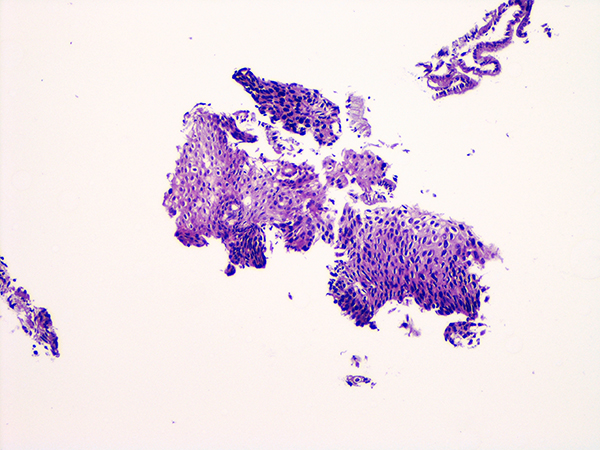

![]() Case 2

Soft Bx CIN 2 10x - Low Power |